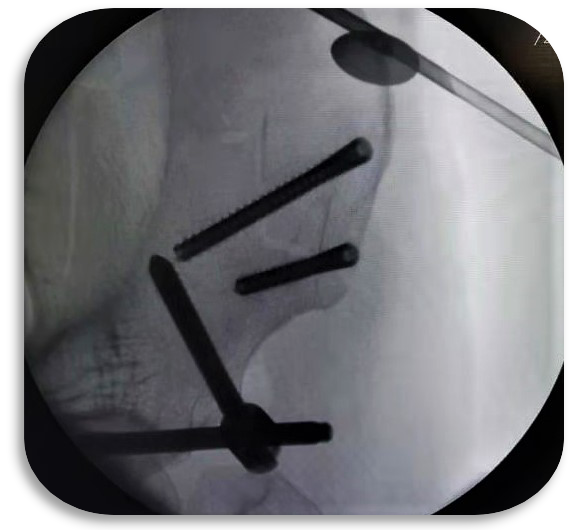

科室设置四个亚专业:创伤骨科以微创开展复杂骨折与多发伤救治,实现骨折愈合与功能恢复同步;手足显微外科凭精细显微操作,开展断指(肢)再植、血管神经损伤修复,游离皮瓣移植创面修复,各类手足畸形矫治;关节与骨质疏松组遵循阶梯化治疗,开展保关节、微创关节置换及各类关节翻修手术,骨质疏松专业实现骨质疏松全生命周期管理,规范抗骨质疏松治疗切实降低骨折风险,改善骨质健康;运动医学专业以关节镜微创技术为核心,诊治各种运动系统损伤,结合康复疗法助力患者重返运动。